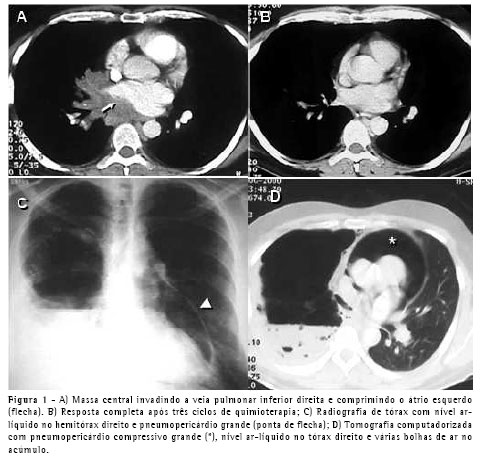

Um paciente do sexo masculino, com 64 anos, apresentando doença pulmonar obstrutiva crônica foi submetido a enxerto bypass de artéria coronária (EBAC) com anastomose de artéria mamária interna direita. Na unidade de terapia intensiva, duas horas após a extubação, ele apresentou pneumotórax espontâneo à esquerda, o qual foi controlado através da inserção de um cateter pigtail 14 Fr, após o quê o paciente melhorou. Porém, dois dias depois, ele apresentou desconforto respiratório e um segundo pneumotórax foi visto apesar do fato de que o cateter pigtail havia permanecido na cavidade pleural e encontrava-se desobstruído. Um segundo cateter pigtail foi inserido em posição anterior.

O problema foi resolvido, e os cateteres foram removidos. No dia seguinte, o paciente apresentou hipotensão, taquicardia e dispnéia. Por motives técnicos, não foi possível realizar um ecocardiograma. A TC mostrou um pneumotórax anterior esquerdo e um pneumopericárdio grande (Figura 2). Um tubo torácico 32 Fr foi inserido na cavidade pleural esquerda, e o problema foi totalmente resolvido. O paciente também foi submetido a uma pleurodese com talco em suspensão. A mesma solução simples (drenagem pleural) foi usada neste segundo caso.